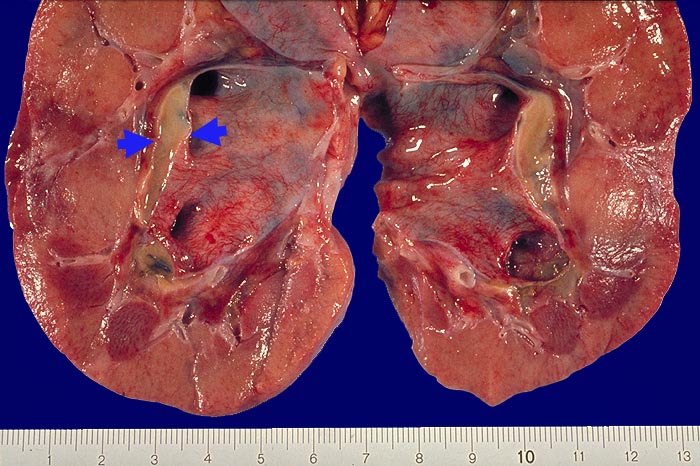

PathoPic – image database / PathoPic ID 1760 - Akute Pyelonephritis: subpelvine Phlegmone bei akuter Pyonephrose.

Akute Pyelonephritis: subpelvine Phlegmone bei akuter Pyonephrose.

Die Nierenbeckenschleimhaut zeigt eine massive Gefässinjektion. Zwischen Nierenparenchym und Nierenbeckenschleimhaut ist im subpelvinen Fettgewebe ein ► Eiterband erkennbar. Im Nierenparenchym nur kleinste akute pyelonephritische Herde.